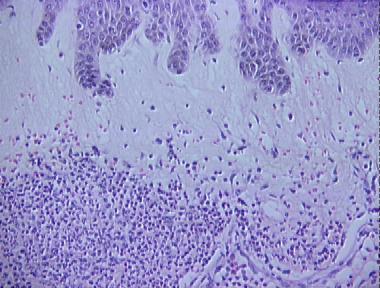

Sweet's syndrome (acute febrile neutrophilic dermatosis)

Histologic Features